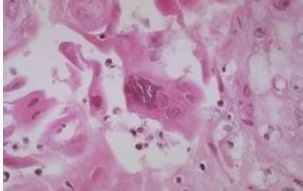

4.组织学检查

前面说过猫结膜炎是猫疱疹病毒的一大症状,还有另一个症状也比较突出,那就是口舌溃疡。

口舌溃疡

做好结膜涂片以及口舌溃疡组织学检查对于FHV-1的诊断也大有裨益。